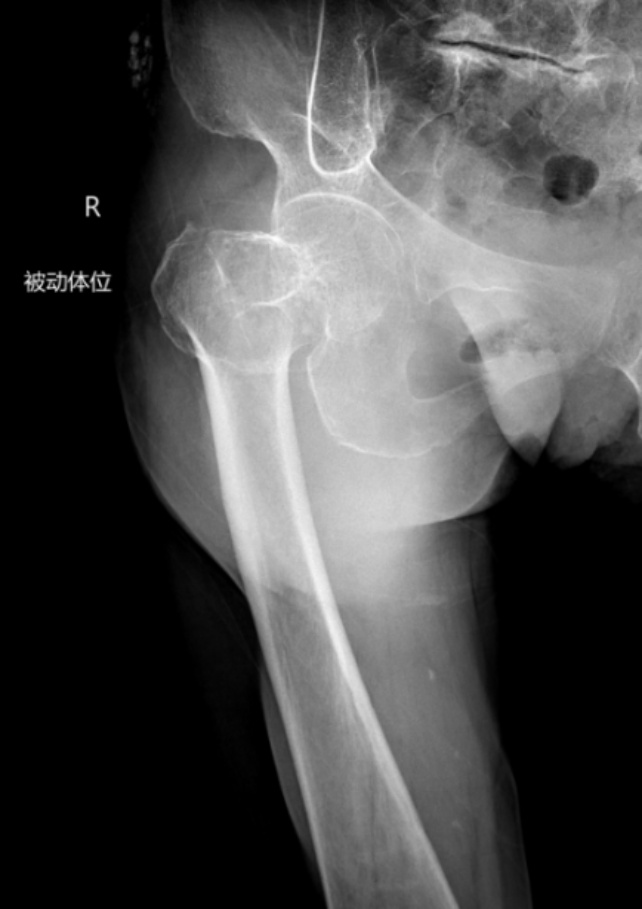

典型病例影像学表现见图1~10。图1为86岁女性右侧股骨转子间骨折(Evans Ⅲ型)患者,术前X线示骨折断端部分错位,术后X线示骨折位置可以及假体位置良好;图2显示了一名81岁男性患者,诊断为左侧股骨转子间骨折,类型为Evans V型,合并股骨干陈旧性骨折。患者接受了生物型加长柄半髋关节置换手术,并进行了股骨近端的钢丝捆扎内固定。术后X线示假体位置良好,股骨近端予钢丝捆扎固定;图3为87岁女性左侧股骨转子间骨折(Evans V型)患者,术后X线示假体位置良好,股骨大小转子骨折位置可,钢丝捆扎固定在位有效;图4为75岁女性左侧股骨转子间骨折(Evans V型)患者,术前X线示左侧股骨转子间骨折PFNA术后、骨折未愈合、内固定断裂。术后假体匹配良好,股骨近端钢丝内固定稳定可靠;图5为75岁男性左侧股骨转子间骨折(Evans IV型)患者,术后股骨大转子出现轻度位移,假体位置正常。图6为87岁男性左侧股骨转子间骨折(Evans V型)患者,给予DAA入路加长柄半髋关节置换,术前X线片,清晰地显示出左侧股骨转子间的骨折情况,术后X线影像,显示股骨的大小转子骨折位置良好,钢丝内固定装置在位稳定,假体位置良好;图7为77岁女性右侧股骨转子间骨折(Evans V型)患者,术前X线片显示右侧股骨转子间存在骨折且股骨大小转子均有累及和移位,术后X线片显示股骨小转子轻度移位,内固定装置位置稳定,假体位置良好;图8为70岁男性左侧股骨转子间骨折(Evans III型)患者,术前的X线片,清晰地显示了左侧股骨转子间的骨折情况,股骨近端髓腔钙化灶,术后假体位置满意;图9为77岁女性右侧股骨转子间骨折(Evans V型)患者,术前X线片,显示右侧股骨转子间及转子下部位骨折情况。术后假体匹配良好;图10为71岁男性右侧股骨颈骨折(Evans IV型)患者,术前X线片,显示右股骨转子间骨折的情况;术后X线表明股骨的大转子和小转子骨折位置保持良好,内固定装置稳固,术后假体位置正常。

Figure 3. An 87-year-old female patient with left intertrochanteric fracture of the femur (Evans V type). (a) Before surgery; (b) After surgery

3. 87岁女性左侧股骨转子间骨折(Evans V型)患者。(a) 术前;(b) 术后